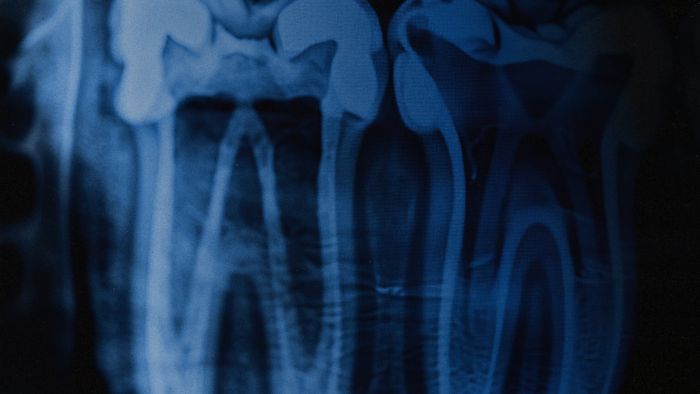

У полоні ворог намагається зламати людину не лише психологічно, а й фізично. Обличчя та зуби часто стають ціллю для катувань — за статистикою, кожен третій, хто пройшов через тортури, має важкі травми щелепи.

Більшість ветеранів, що пройшли через полон, мають критичний рівень тривожності. Звичайний візит до лікаря може обернутися ПТСР-нападом або важким флешбеком. Саме тому стоматологічна реабілітація військових у межах ініціативи Re:Smile будується на тандемі лікаря та психолога.

Ми працюємо з наслідками катувань, де кожен рух медика має бути виваженим. Це не просто про «поставити пломбу», а про комплексне відновлення функції жування та психоемоційного стану. Коли людина знову може впевнено говорити й посміхатися — це перший крок до виходу із соціальної ізоляції.

● Повну діагностику та складання плану реконструкції щелепи;

● складне протезування та імплантацію за сучасними стандартами;